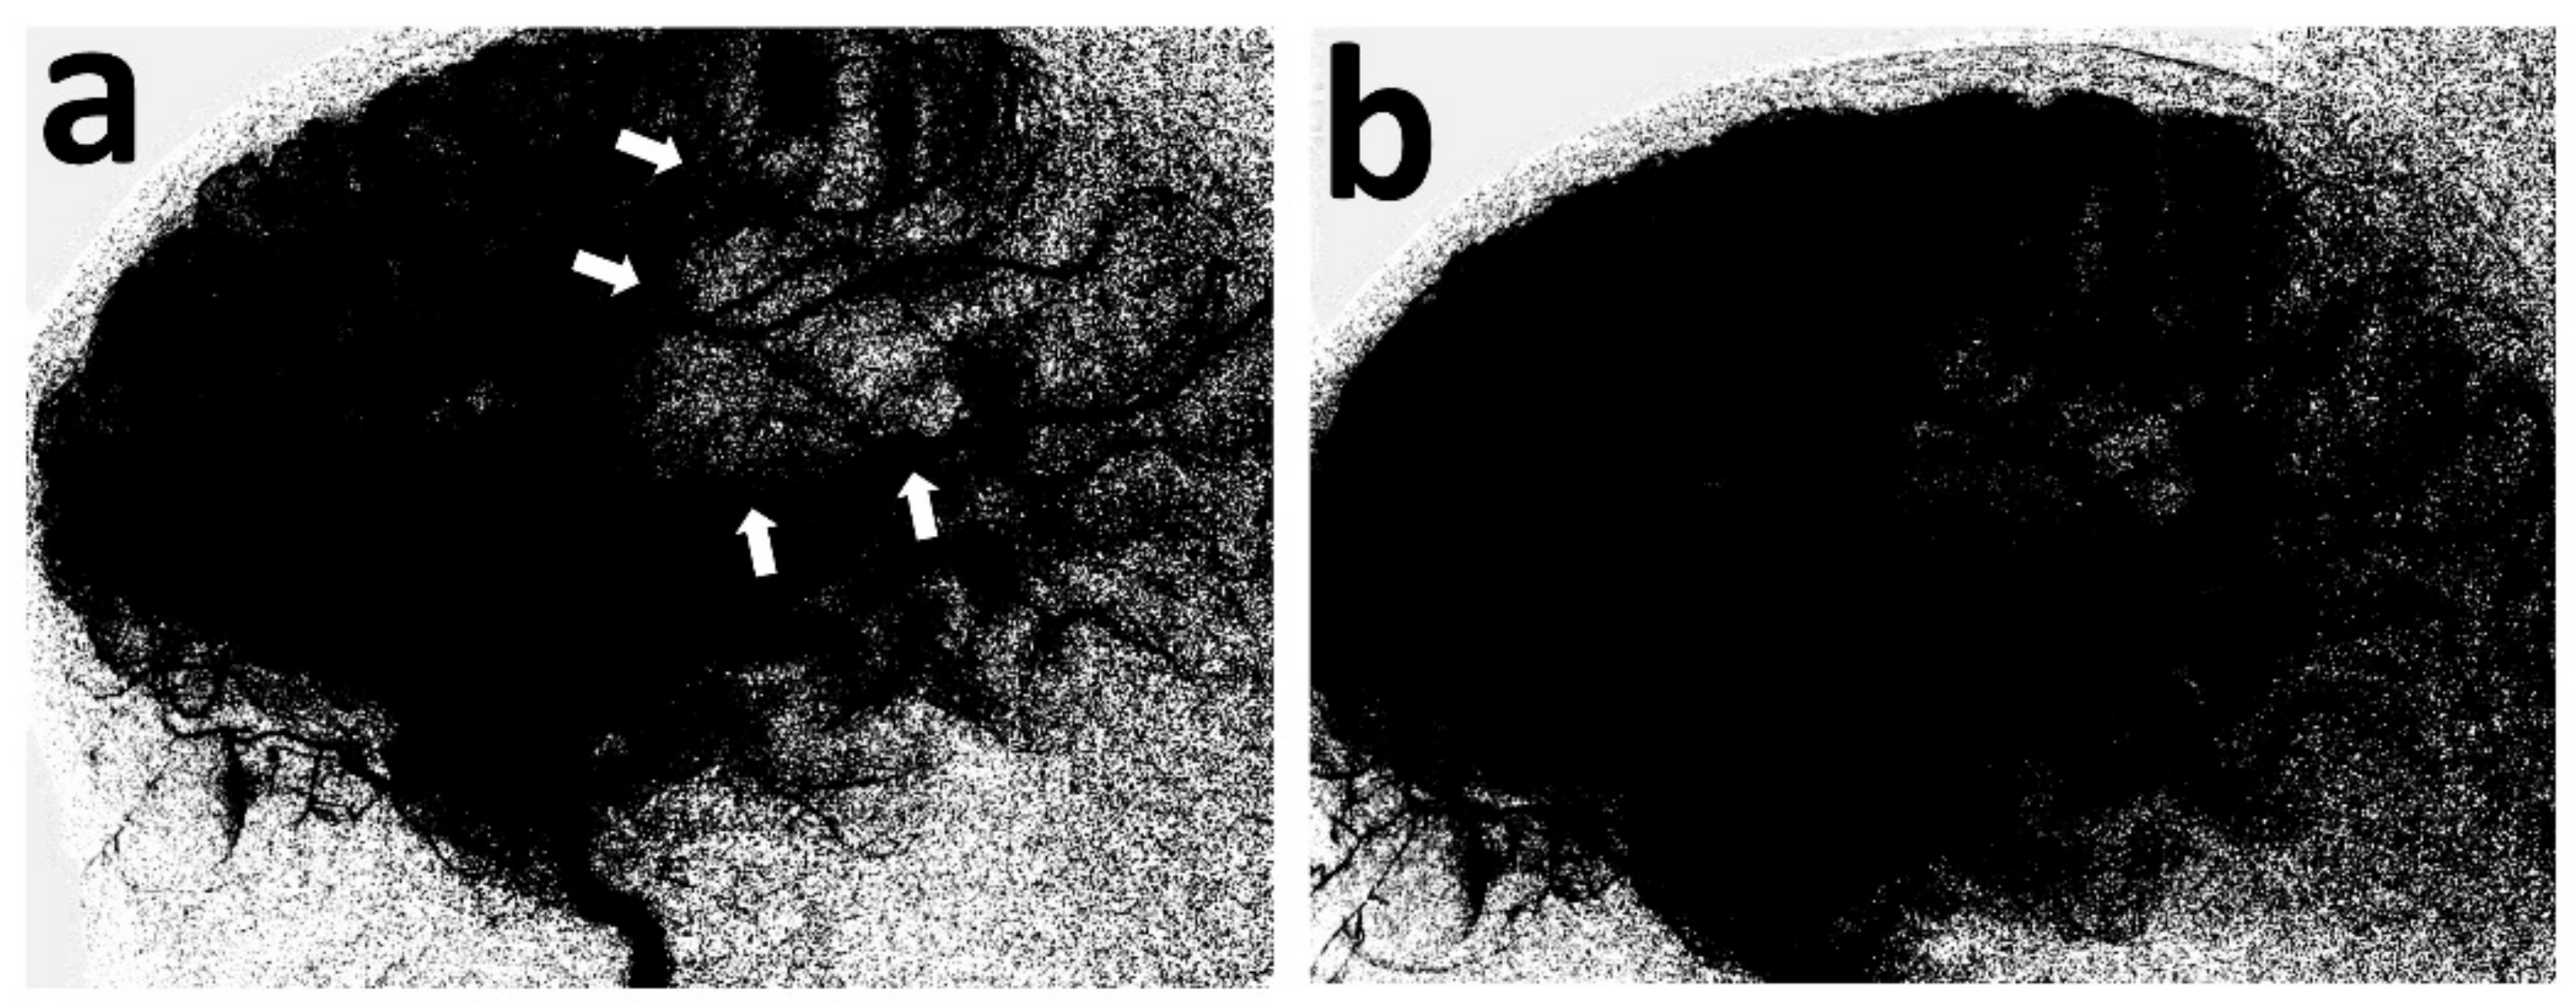

Figure 3.

Lateral view of the digital parenchymography, before and after thrombectomy. At baseline, it demonstrates the lack of opacification of the MCA (md) territory (a) (white arrows), which materially opacifies, following removal of the retriever (b).